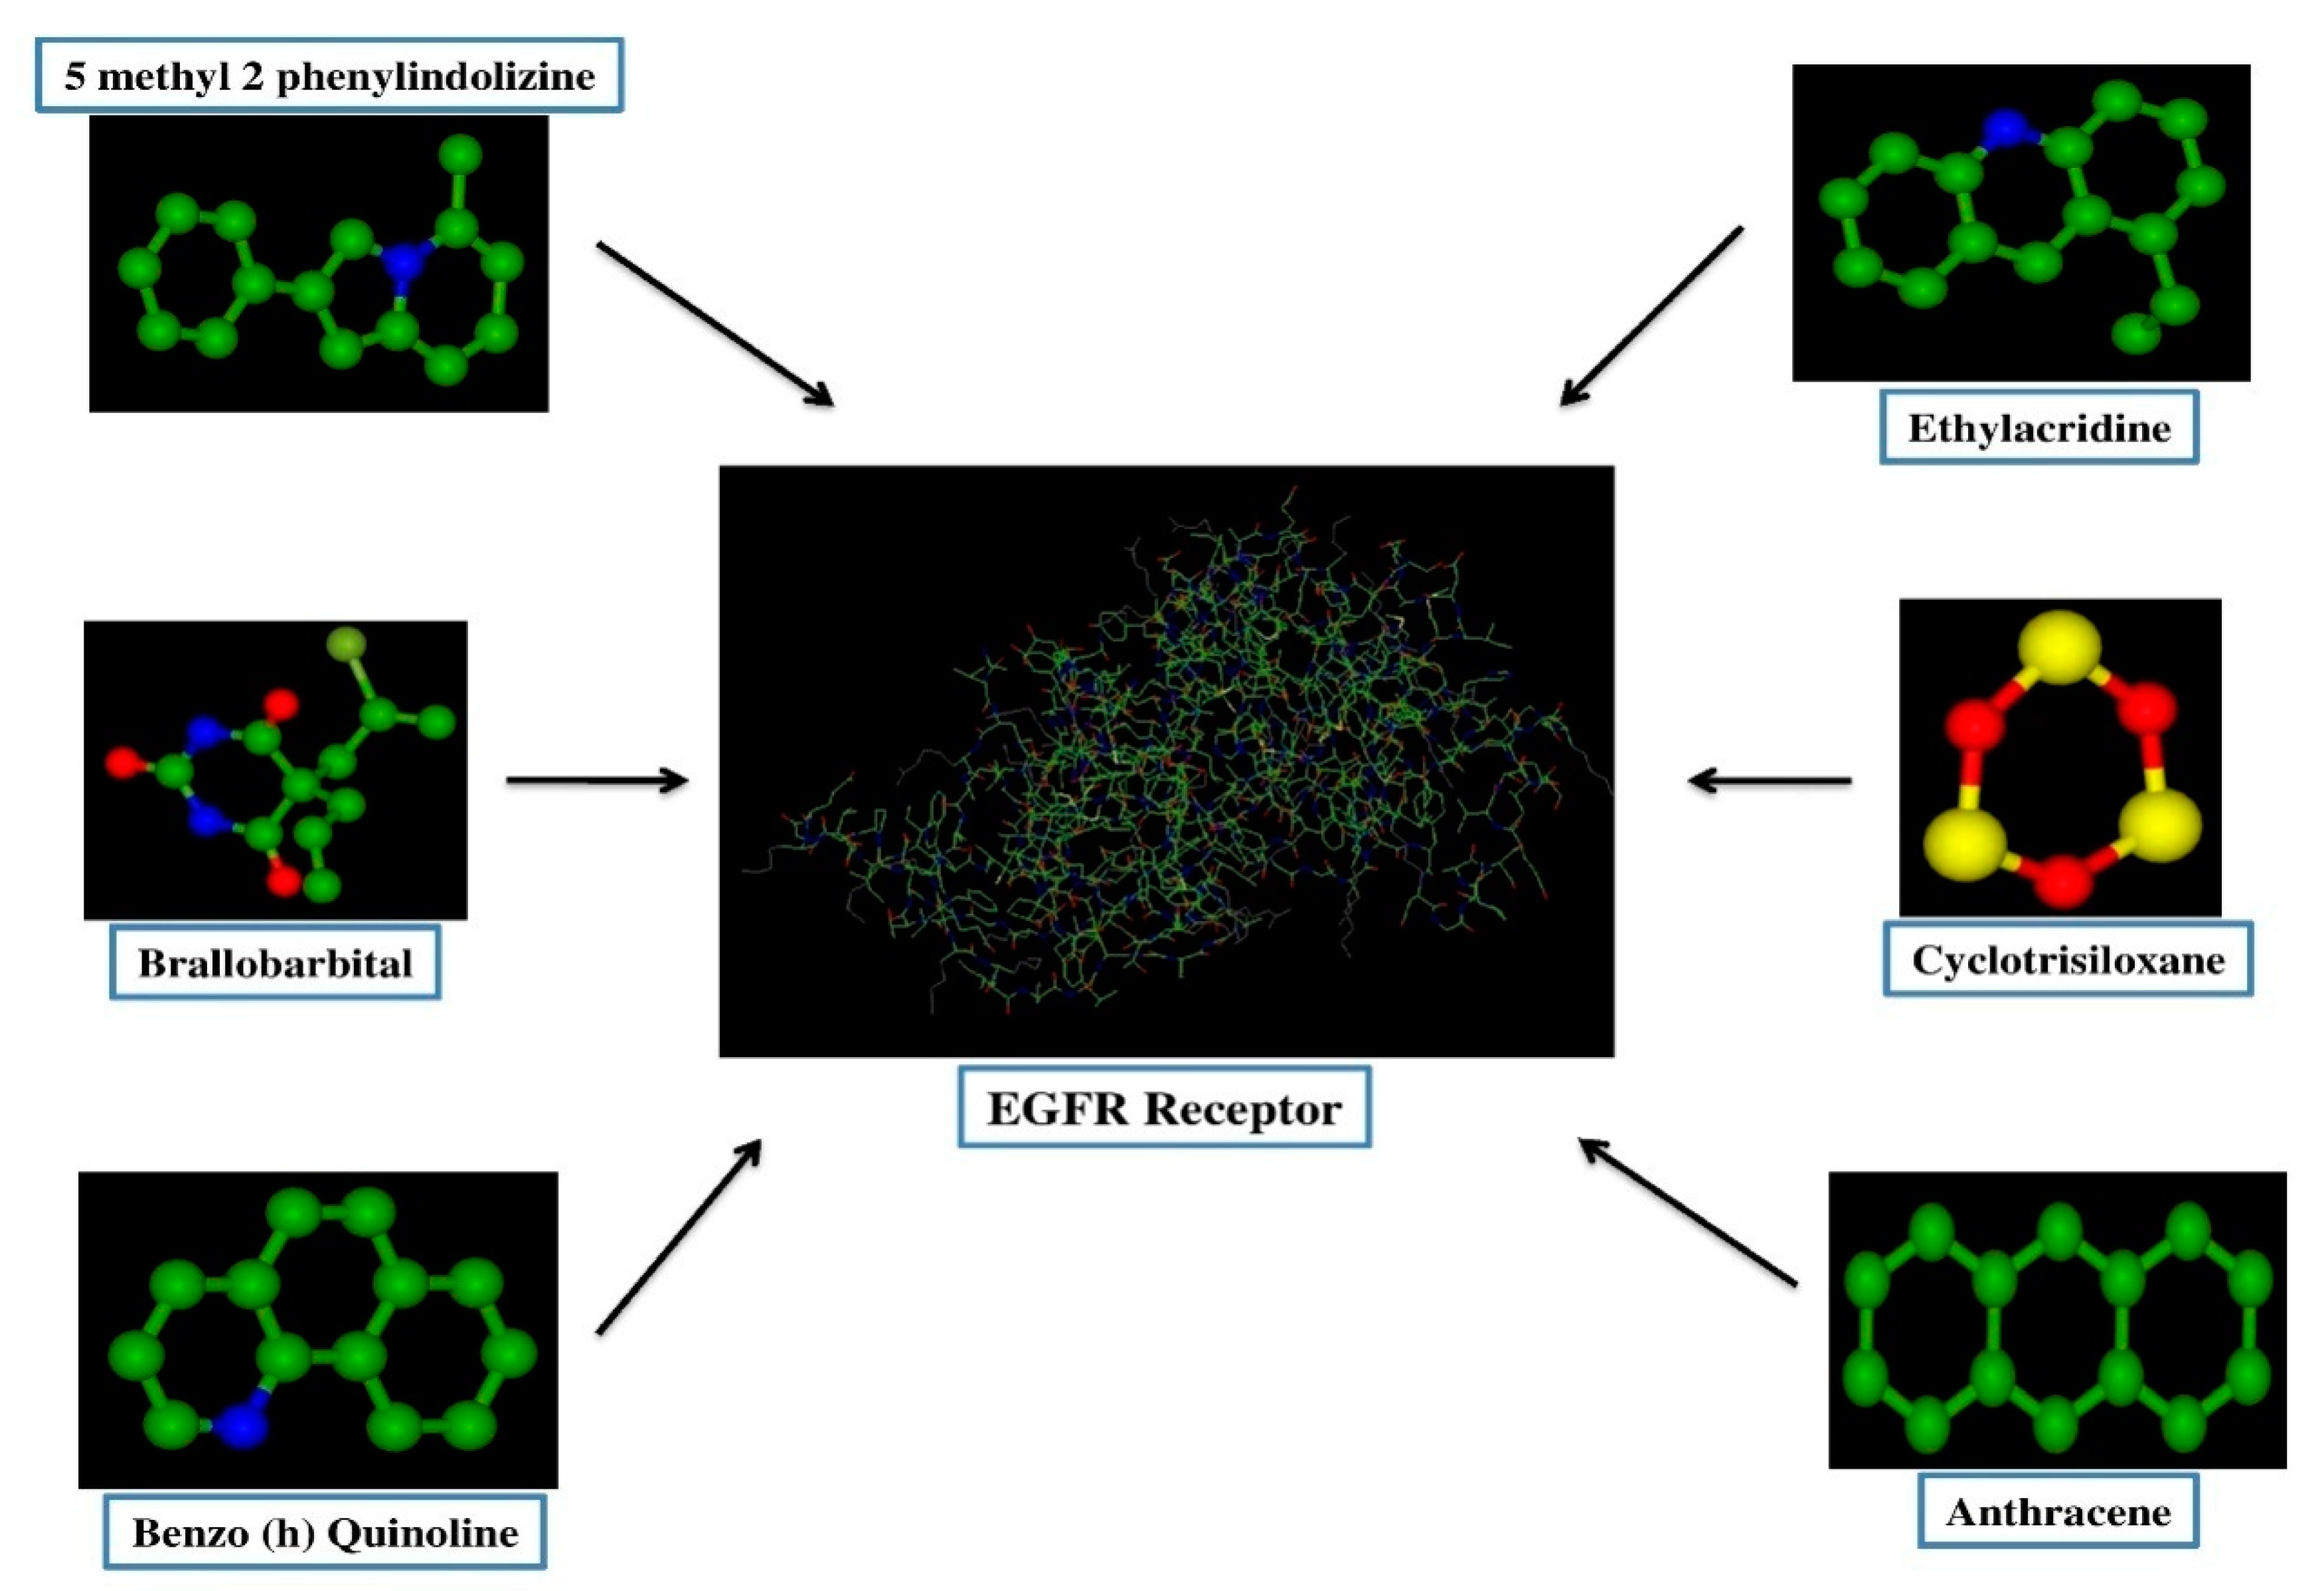

3.6.3. Molecular Docking Study

| Ligand | E min |

|---|---|

| Benzo [h] quinolone | −213.20 |

| Cyclotrisiloxane | −146.53 |

| Ethylacridine | −213.24 |

| Anthracene | −199.45 |

| 5 methyl 2 phenylindolizine | −224.85 |

| Brallobarbital | −227.89 |